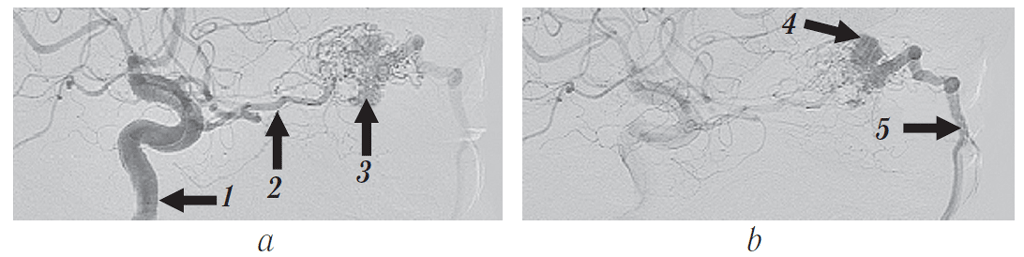

Согласно рекомендациям нейрохирурга выполнена селективная церебральная ангиография. В области правой орбиты выявлена интенсивная патологическая сосудистая сеть новообразования диаметром до 3 см, получающая кровоснабжение из правой глазной артерии с дренированием в правую лицевую вену (см. рис. 12, 17, a). Заключение: «Ангиографическая картина гиперваскуляризированного образования правой орбиты с питанием из ветвей правой глазной артерии».

Рис. 12. Ангиограмма правой внутренней сонной артерии и сосудов правой глазницы, сагиттальная проекция: а — артериальная и b — венозная фазы. 1 — правая внутренняя сонная артерия. Сосудистая сеть новообразования (а и b, 3) получает питание из расширенной глазной артерии (а, 2) с дренированием в правую лицевую вену (b, 4)

Fig. 12. Angiogram of the right internal carotid artery and the vessels of the right orbit, sagittal projection: a — arterial phase, b — venous phase: 1 – right internal carotid artery. The vessels of the neoplasm (а and b, 3) are fed from the dilated ophthalmic artery (а, 2) with drainage into the right facial vein (b, 4)

При контрольной ангиографии (рис. 16, 17, b) отмечено отсутствие контраста в сосудистой сети опухоли с выраженным замедлением тока крови по дренирующей вене и приводящей ветви глазной артерии. Церебральные ветви проходимы, диаметр и топография их сохранены.

Рис. 16. Контрольная ангиограмма правой внутренней сонной артерии и сосудов правой глазницы, сагиттальная проекция: артериальная (а) и венозная (b) фазы. В артериальную стадию (a) контрастируется глазная артерия (2), сосудистая сеть новообразования не определяется. В полости образования в обе стадии ангиографии (a и b) визуализируются рентгеноконтрастные эмболизирующие микроспирали (5). В венозную стадию (b) отток из опухоли в правую лицевую вену отсутствует (4)

Fig. 16. Control angiography of the right internal carotid artery and vessels of the right orbit, sagittal projection: arterial phase (a) and venous phase (b). At the arterial phase (a), the ophthalmic artery is contrasted (2), the vascular network of the neoplasm is not detected. In the cavity of the tumor in both stages of angiography (a and b), radio opaque embolizing microspirals (5) are visualized. At the venous phase (b), there is no outflow from the tumor into the right facial vein (4)

Рис. 17. Динамика заполнения сосудистой сети новообразования глазницы контрастом по результатам ангиографии: а — до эмболизации: постепенное заполнение артериальной сети церебральных сосудов, а затем и сосудов опухоли с переходом в венозную фазу; b — после эмболизации

Fig. 17. Dynamics of filling of the vascular network of the orbital neoplasm with contrast according to the results of angiography: a – before embolization: gradual filling of the arterial network of the cerebral vessels and then those of the tumor with the transition to the venous phase; b – after embolization

Поэтапная динамика заполнения церебральных сосудов и сосудистой сети новообразования глазницы контрастом в ходе ангиографии до и после эмболизации сосудов новообразования показана на рис. 17.